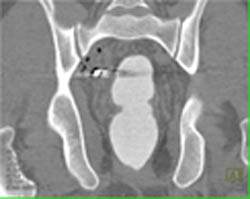

Diagnosis

Normal Aortic Valve Replacement -closed/open